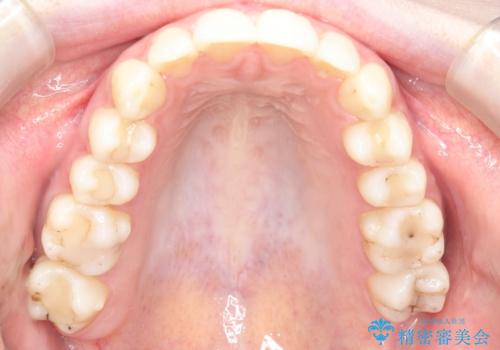

【インビザライン】前歯のガタガタをなおしたい。

- 前歯の凸凹を主訴に来院されました。

インビザラインにて奥歯の遠心移動を行いながら、前歯のガタガタを改善することができました。